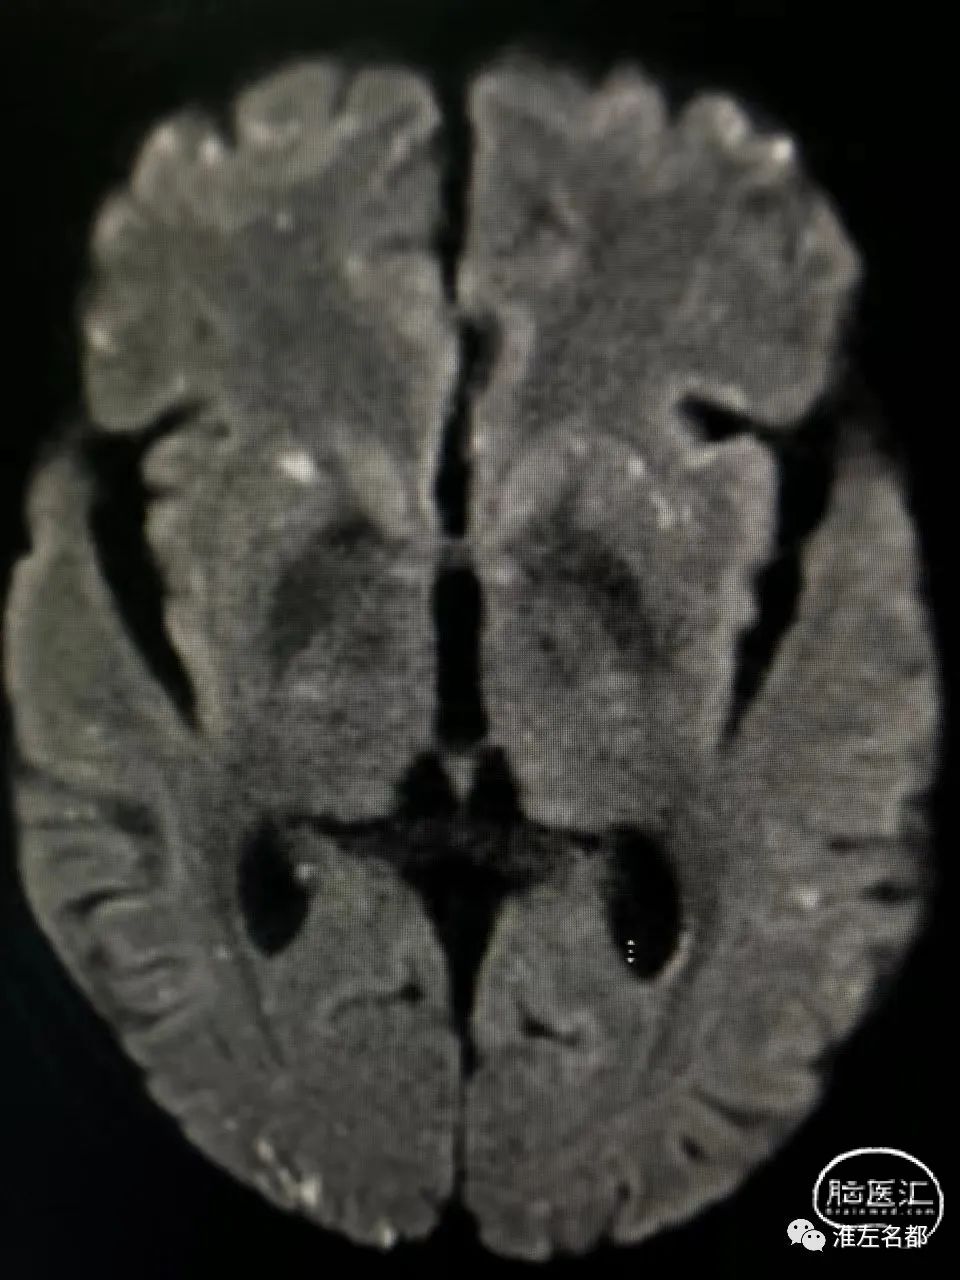

脑DWI:双侧半球皮质和皮质下弥漫分布的点状急性微小梗死灶。

第一,心源性栓塞梗死:患者心电图、心脏超声和心梗组合均提示心肌梗死,而心肌梗死是重要的心源性脑栓塞原因;该患者急性梗死病灶累及双侧半球多个脑动脉供血区,这个特征也是支持心源性栓塞的。

第二,还有一种可能的机制是,与肝癌栓塞治疗相关的反常栓塞:肝癌的肿瘤组织内是可能存在异常动-静脉瘘的,此时微小的球状介入栓塞材料就能通过这种瘘,经肝静脉进入下腔静脉和右心房,如果同时合并卵圆孔未闭,栓塞微球可经未闭的卵圆孔进入体循环,进而栓塞全身各个器官,包括脑和心脏。上述机制的支持点包括:患者53岁中年男性,而很大比率中-青年人群会合并卵圆孔未闭;患者术前无心脏疾病和心血管危险因素,术后即胸闷气促,这可能与介入用微球栓塞心肺的供血血管有关;由于微球直径很小,只会导致脑动脉远端的微小血管闭塞,所以脑梗死的范围很小,且弥漫分布。